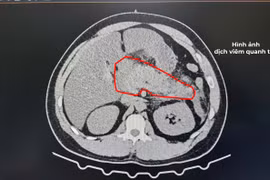

Bệnh viện Đa khoa Trung tâm tỉnh Gia Lai vừa cứu sống bệnh nhân viêm tụy cấp biến chứng sốc nhiễm khuẩn, suy đa tạng nhờ áp dụng kỹ thuật lọc máu liên tục.

Lọc máu hấp phụ được xem là một trong những phương pháp hiện đại, điều trị hỗ trợ hiệu quả, các trường hợp viêm tụy cấp thể nặng có biến chứng suy đa tạng, giúp loại bỏ các yếu tố trung gian gây viêm khỏi tuần hoàn máu.

Viêm tụy cấp do tăng mỡ máu thường nặng hơn và đe dọa tính mạng bệnh nhân hơn so với các nguyên nhân khác. Lọc máu liên tục là phương pháp mới hạn chế được nhược điểm của phương pháp thay huyết tương.